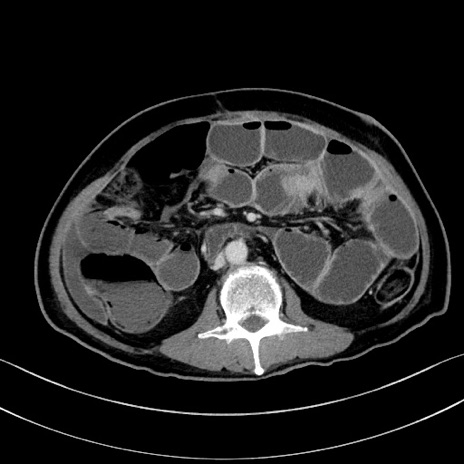

症例28(横断像)

【症例】60歳代男性

【主訴】嘔吐

【現病歴】胃癌にて胃全摘後。食思不振が悪化し、夜中に嘔吐することがある。

【既往歴】胃癌、胃全摘、脾摘、胆摘後

【データ】WBC 5900、CRP 10.56